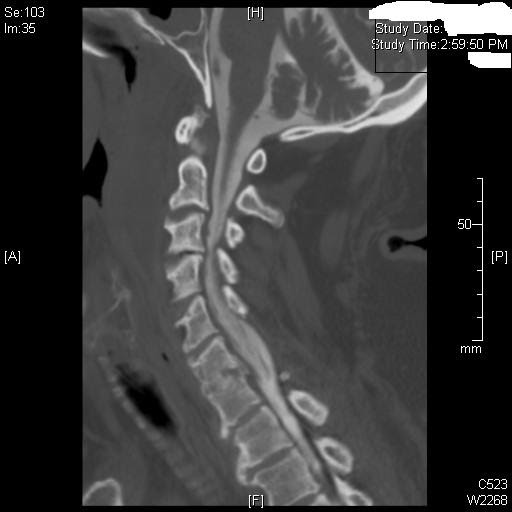

From ctprocedures.blogspot.com

CT Pathology Blog Cervical disc bulge Cervical Disc Bulge Reddit To manage a bulging disc, it’s crucial to incorporate specific exercises that target the spine’s support system. Has anyone had a bulging disc in their neck? We’ve gathered some exercises that encourage healing as well as those you should avoid. a bulging disc in the neck occurs when a spinal disc weakens and encroaches on the spinal. poor. Cervical Disc Bulge Reddit.